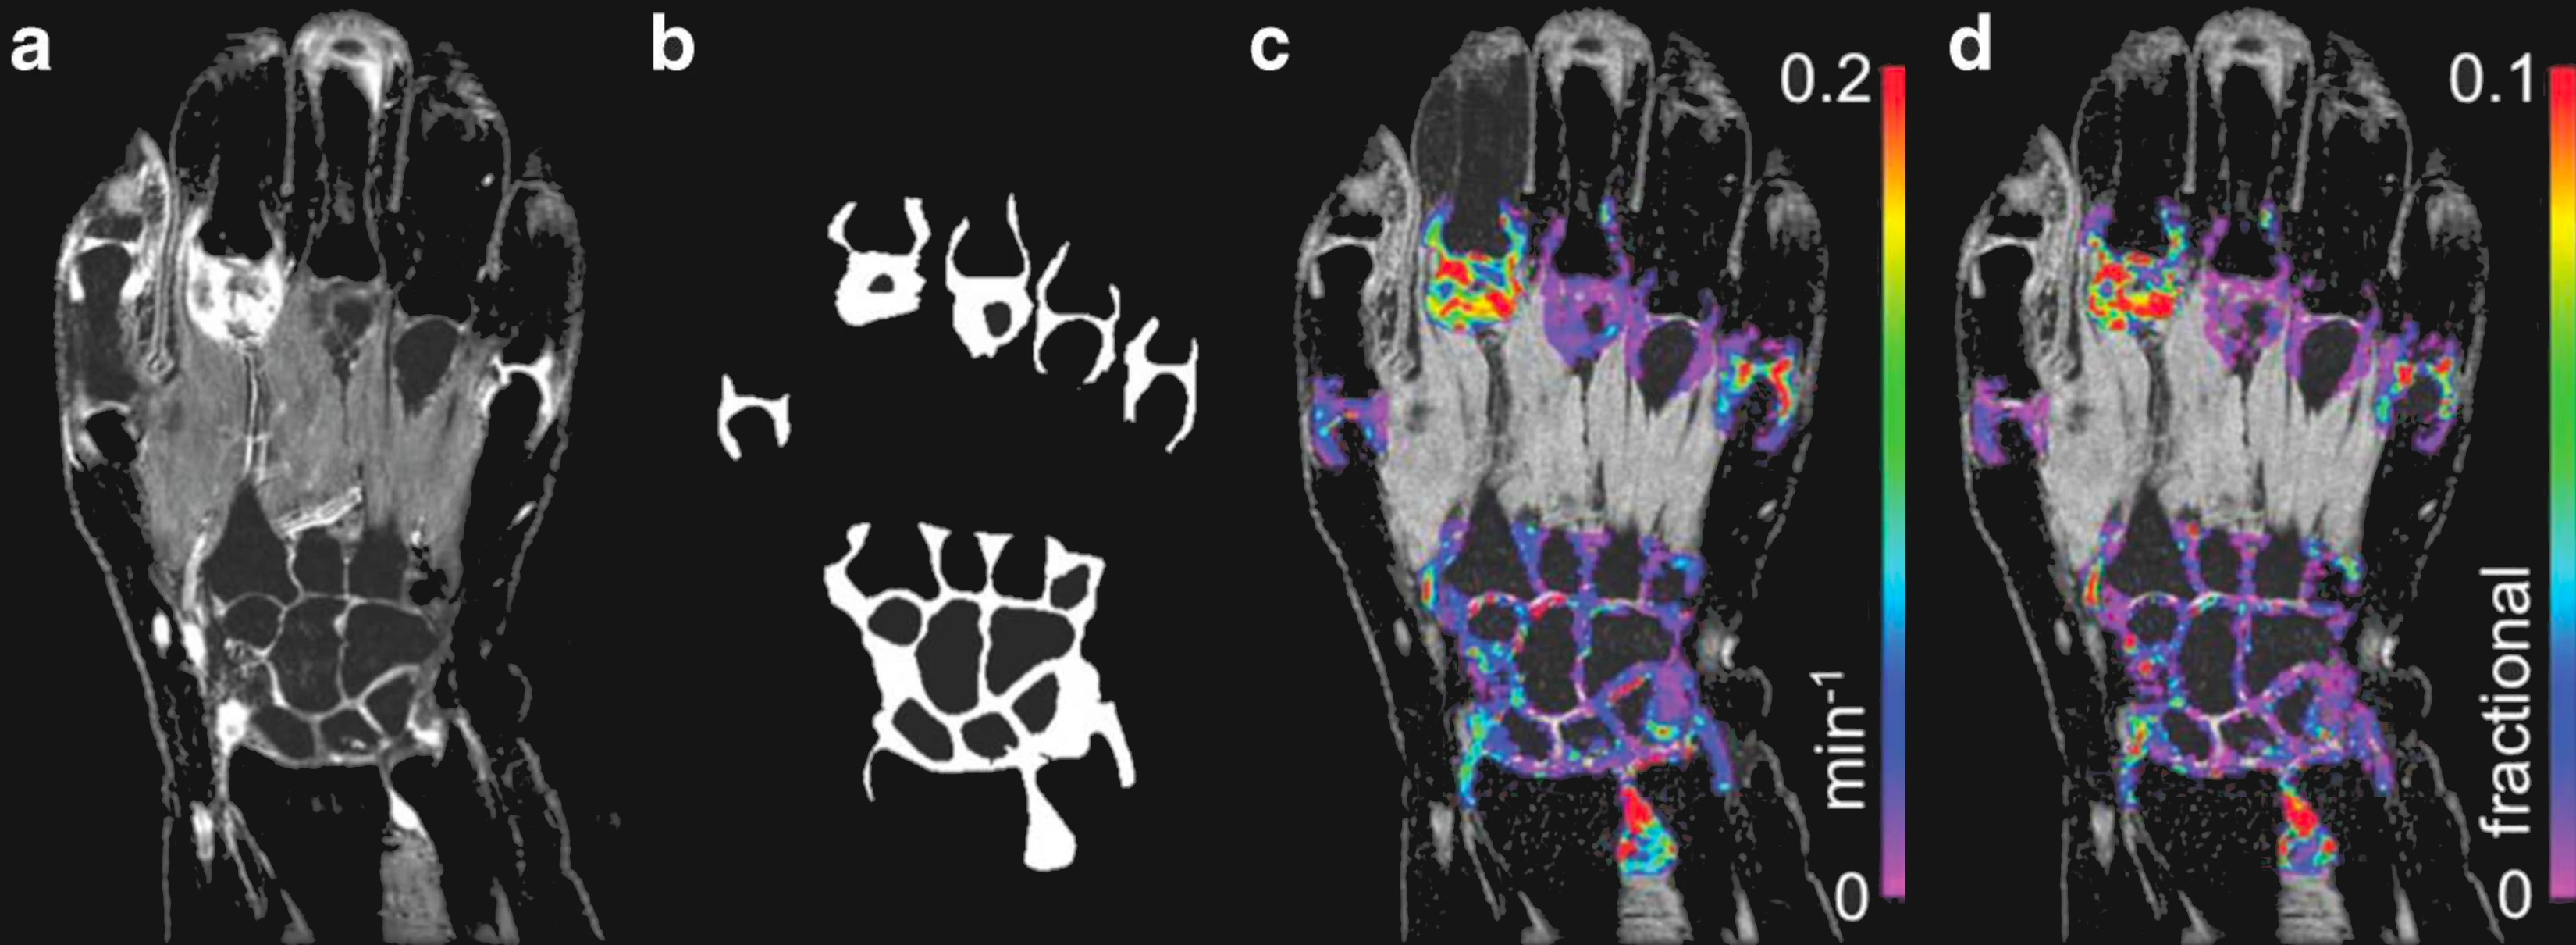

From study design to final reporting, Bioxydyn delivers repeatable MRI biomarkers that reveal tissue function, physiology and change. Our operational excellence and metrology help you compare results across sites, scanners and timepoints.

We're Bioxydyn - delivering quantitative MR biomarkers for pharmaceutical, biotech and academic studies. We combine scientifically leading methods with robust multi-centre study management and transparent analysis, turning complex images into repeatable measurements that support confident decisions.

VoxelFlow supports your clinical trial end-to-end, delivering reliable, repeatable and auditable outputs. It is compliant with FDA 21 CFR Part 11

Disease areas and services supporting quantitative MRI biomarkers across clinical trials.